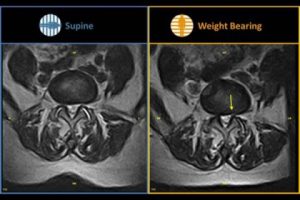

Unique Weight-Bearing MRI Capabilities

Weight-bearing studies are easy to perform, allowing patients to be imaged in the position in which they experience symptoms and providing documentation that can be critical in pre-surgical workflow.